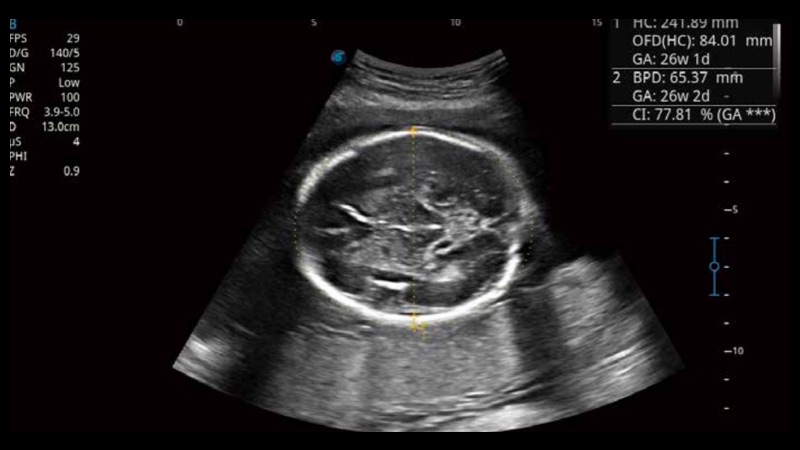

S-Fetus基于大數(shù)據(jù)深度學(xué)習(xí)算法,能夠幫助您在產(chǎn)前篩查過程中智能識別胎兒標(biāo)準(zhǔn)切面、自動測量并錄入報告。一個按鍵,即可智能、精準(zhǔn)、高效地獲取胎兒生理指標(biāo),極大簡化您的產(chǎn)科檢查操作。

可快速對產(chǎn)科掃查切面完成胎兒生理學(xué)參數(shù)的自動測量,減少操作者按鍵次數(shù),大幅提升檢查效率。